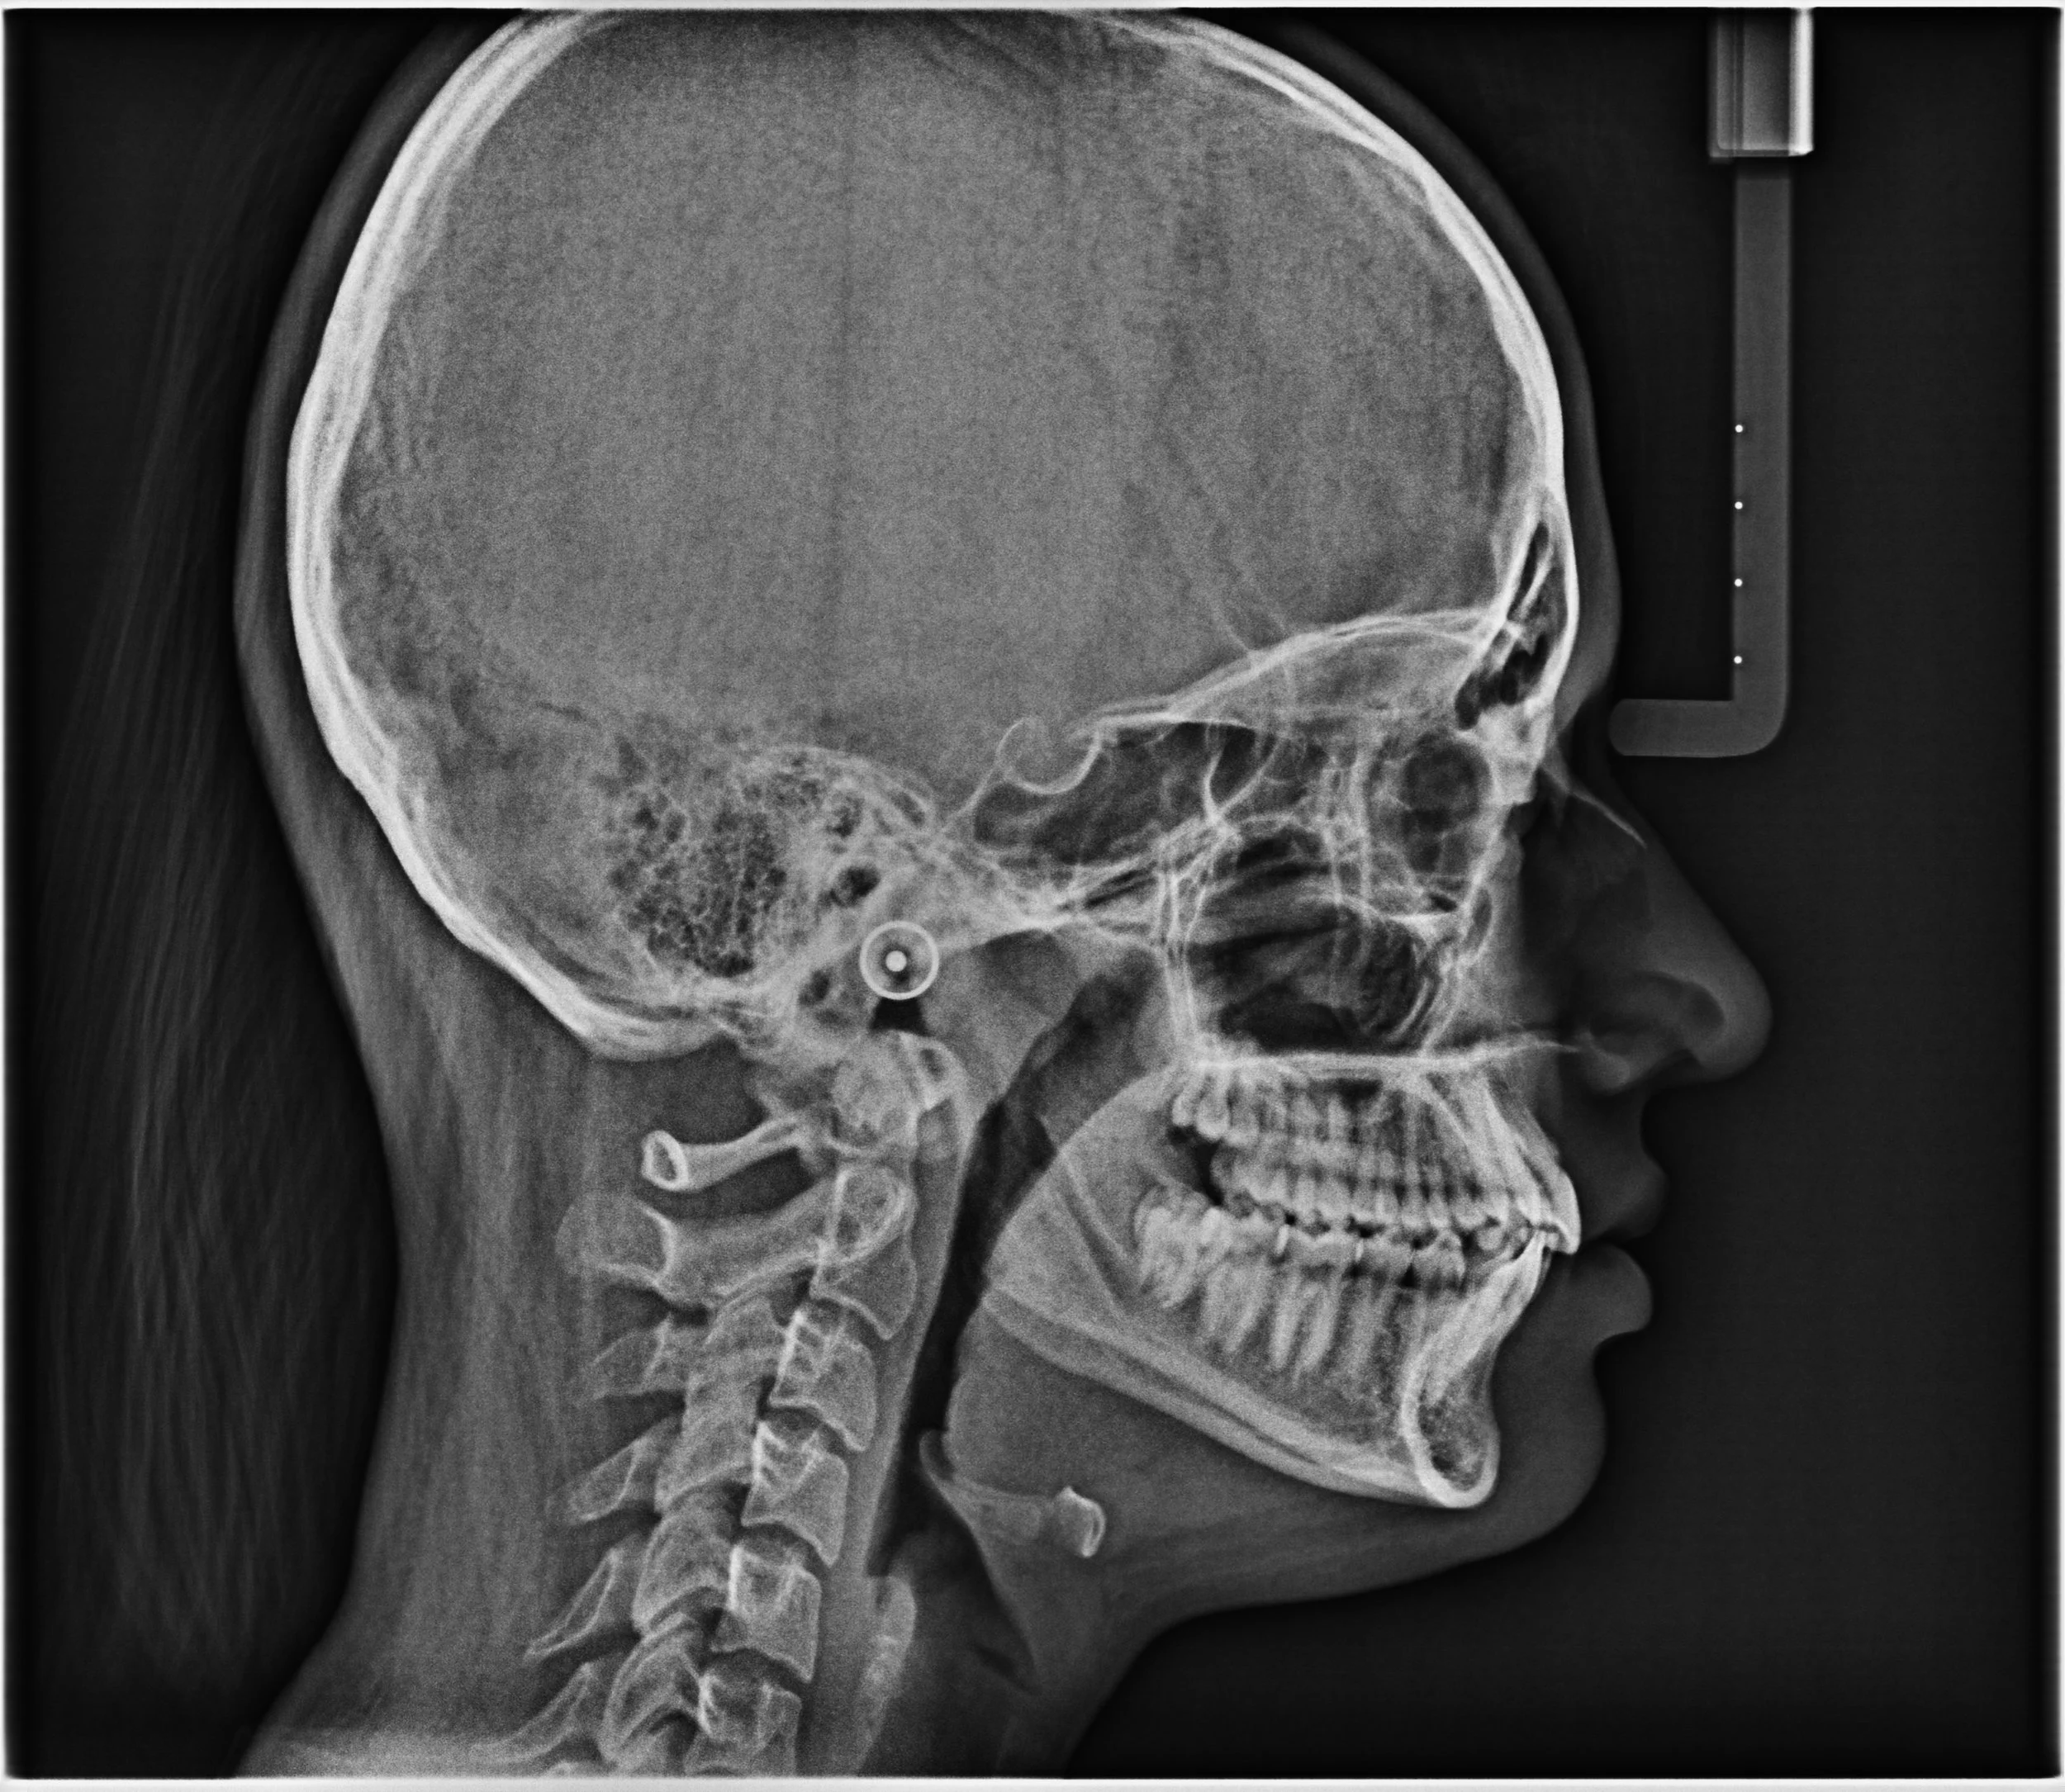

Lateral Ceph

Cephalometry

The cornerstone of good orthodontic practice, cephalometry is a technique sensitive imaging modality. Cephalometric tracing and analysis by a radiologist is inclusive of the cost of your imaging. We also provide other extraoral radiographs like the PNS View, Frontal Cephalogram